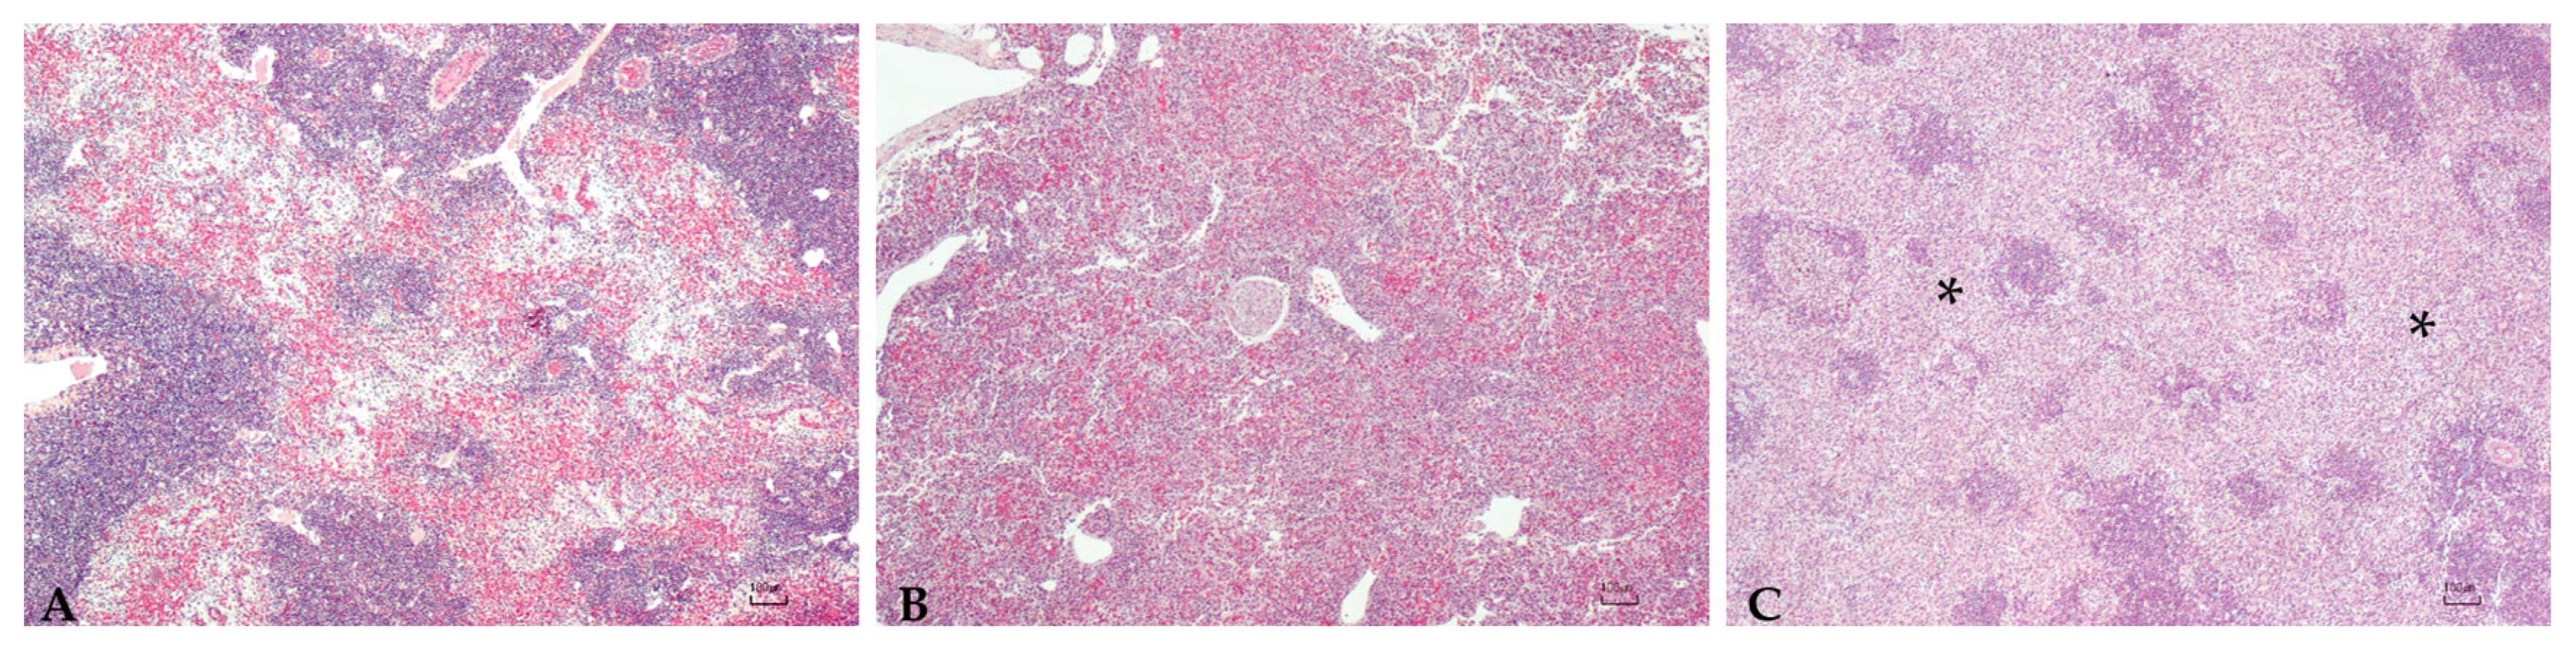

Sturgeons showed mild to severe granulomatous chronic inflammatory reactions ranging from mild to severe degrees in all examined organs. In particular, the hepatic parenchyma was expanded by multifocal to coalescing, multinodular, variable size granulomas mainly located near vessels and bile ducts and extended to the serosal surface in the most severe cases (Figure 1). Mild and diffuse congestion of blood vessels was observed in a single case with mild inflammation. The spleen was diffusely expanded in all sturgeons except in one specimen, by a mild to severe chronic granulomatous inflammation associated with edema and vascular congestion (Figure 2). In two out of four sturgeons, the serosa and the outer muscular layer of the small intestine were characterized by a diffuse granulomatous inflammation, whereas the mucosa and submucosa were unaffected (Figure 3). Results are summarized in Table 2.

Figure 1. Liver: Mild (A), moderate (B), and severe (C) granulomatous chronic hepatitis cantered around the bile ducts and arterial vessels (asterisk, (B)). Granulomas consisted of a high number of macrophages, a moderate number of lymphocytes and plasma cells, scattered eosinophilic granular cells (inset (B)), and occasionally 80–100 µm, round, multinucleated cells with round peripherally-located nuclei with dispersed chromatin and granular eosinophilic cytoplasm (Langhans-type cells) (arrow, inset (C)). H.E. Bar (AC) = 100 µm, inset 10 µm.

The previous paper of Mugetti et al. [28] showed clinical signs consistent with those ready reported regarding A. baerii [8] and A. transmontanus [25]. In this second episode two sturgeons were externally normal, even if the histopathological analysis reported a mild inflammation of the liver and the spleen; other two samples were instead characterized by starvation and skeletal deformities, as already reported for A. transmontanus [26]. Moreover, the multifocal involvement of the liver, spleen, and of the intestine mainly centered around vessels and bile ducts, indicating a systemic granulomatous inflammation, and was reported.

The multinucleated cells are noteworthy. Although seldom reported in the fish inflammatory response of bacterial origin, the specimens herein described were found in association with reactive macrophages. These results suggest that these cells in sturgeons could be part of granulomatous inflammation against bacteria.